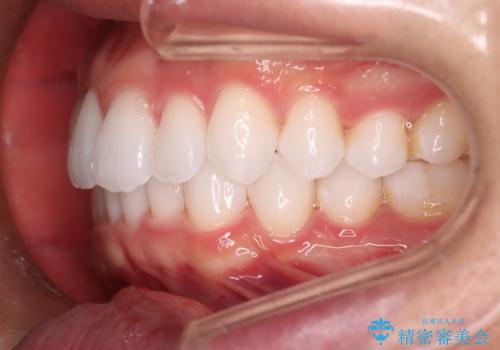

- 20代男性

- インビザライン

- がたつきが気になるとの事で来院されました。

目立たない装置で費用も抑えたいとの希望があったため、インビザラインにて治療をすることとなりました。

上下顎ともにIPR(歯と歯の間を削る処置)を行い歯並びを整える治療計画を立てました。

治療当初は、計画通りに治療が進むか心配でしたが、しっかりマウスピースを使用していただいたことで

治療期間も長引くことなく歯並びを綺麗に改善することが出来ました。

患者様の希望もあり、前歯の微調整で1回リファイメント(マウスピースの再発注)を行いました。